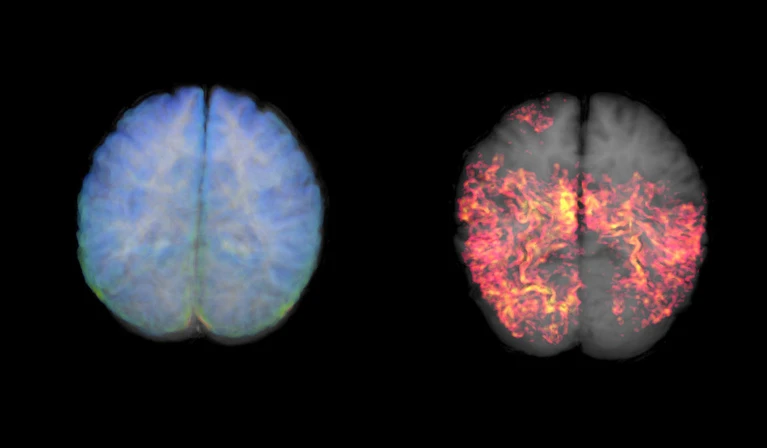

‏Cơ quan Quản lý Thực phẩm và Dược phẩm Mỹ (FDA) vừa phê duyệt loại xét nghiệm máu thứ hai giúp hỗ trợ chẩn đoán bệnh Alzheimer. Liệu những xét nghiệm này có thay đổi cách chúng ta đo lường sự suy giảm nhận thức trong tương lai?‏